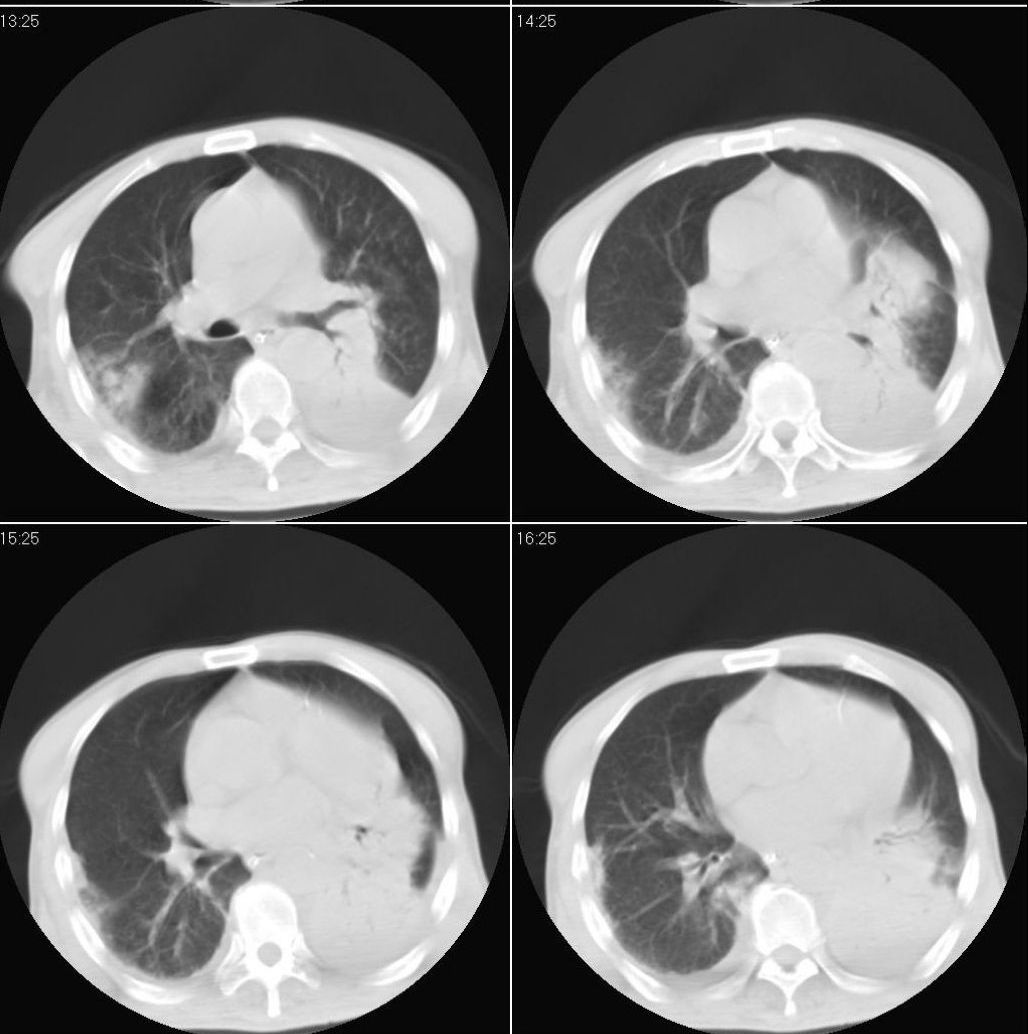

男性,65岁。因外伤来诊。该患者因脑外伤住院。以下是今天的dr和ct:

一周前胸片无异常,不考虑肿瘤,现x片及ct表现应与外伤有关,考虑左侧外伤性膈疝,并左下肺不张。右肺挫裂伤。少量胸水。

一周前胸片无异常,不考虑肿瘤,现x片及ct表现应与外伤有关,考虑左侧外伤性膈疝,并左下肺不张。右肺挫裂伤。少量胸水。支持

1 外伤性左侧膈疝、胸腔积液致左肺下叶不张 2右肺挫伤

右侧第7肋骨腋段骨折并右肺挫伤;左侧膈疝并肺不张。